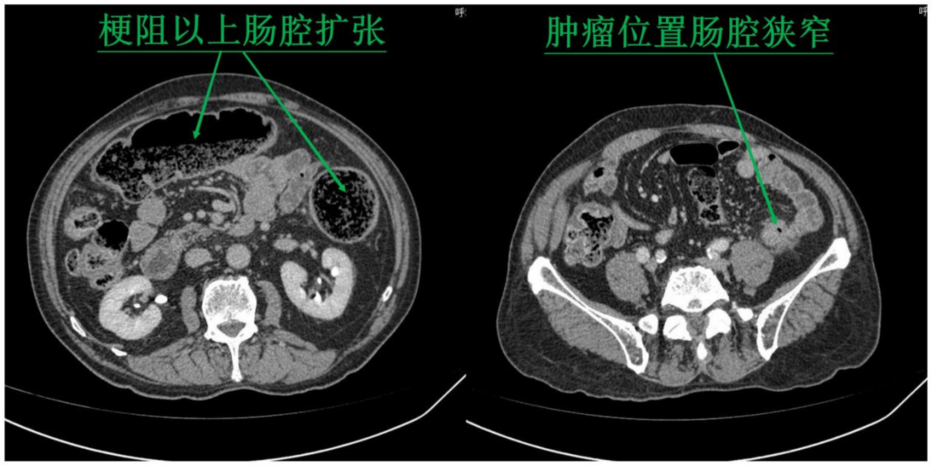

患者男性,89周岁,既往于15年前曾患乙状结肠癌,行传统开腹手术治疗。于2022年4月12日因“腹痛、排便困难4天”再次入院,经检查确诊为“降结肠癌”。肿瘤导致肠腔狭窄,粪便不能通过,肿瘤以上肠管扩张、水肿、积粪。